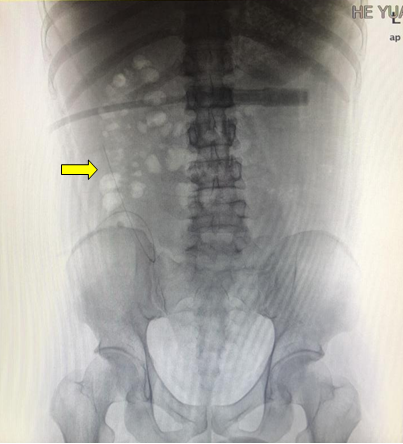

X光片显示腹膜透析导管移位至右侧中腹部(黄色箭头所指为移位的腹膜透析导管尖端,位于右侧中腹部)